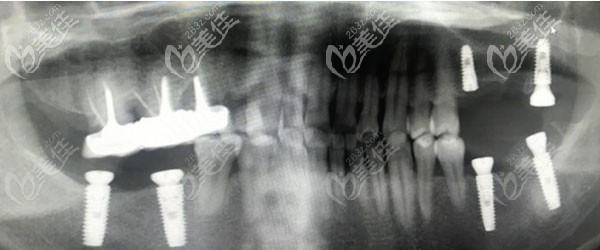

广州皓康口腔——诊所面积约900平米,除开展常规的牙科疾病诊疗,在无牙颌种植修复方面尤为擅长,招牌技术All-on-4即刻种植牙。

特色技术:对于牙槽骨条件不佳的顾客,这里可以仅用4颗植体就能半口牙齿的生理功能,可以较大程度的避免做植骨手术,而且力学功能和美观都比较良好。